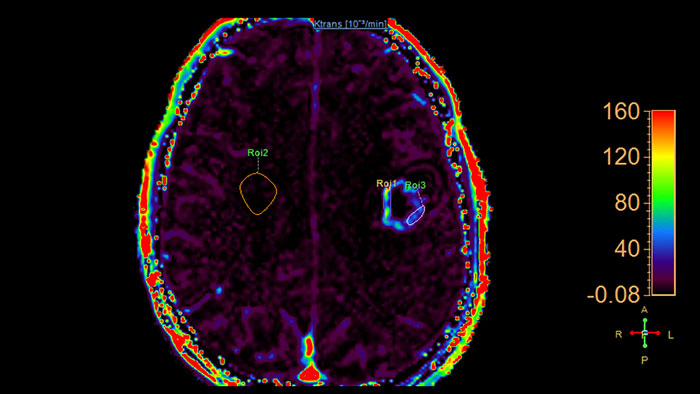

Lesion characterization by reviewing vascular leakage

Designed to visualize T1 weighted DCE 3D datasets and assist in analyzing the tissue response.

Support in assessing lesions by reviewing blood supply characteristics

Designed to evaluate time intensity curves of a T1 signal enhancement series. The application produces measurements including relative enhancement, maximum enhancement, time to peak (TTP), and wash-in/wash-out rates.